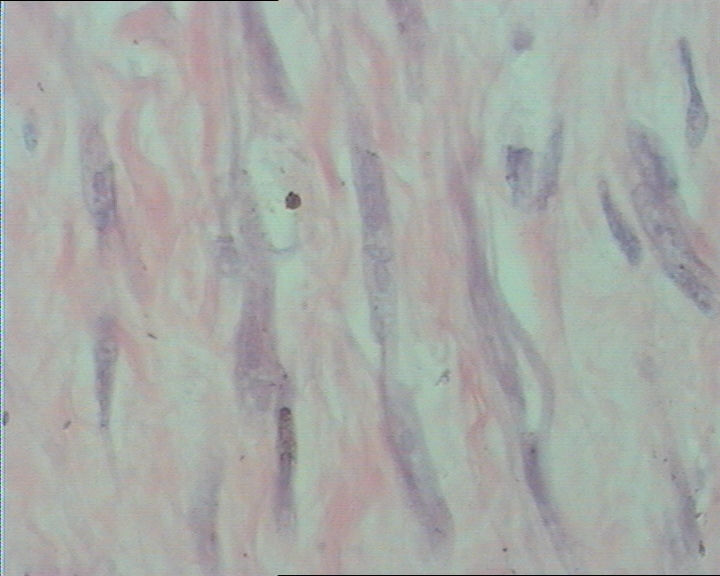

右肘部肿物

图3

右肘部肿物,无包膜,3.8cm*3.0cm*2cm,切面灰白淡黄相间。